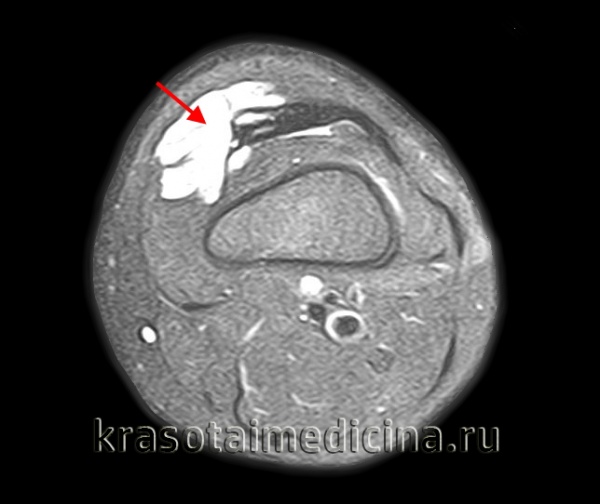

(Слева) МРТ Т1ВИ, аксиальный срез: определяется крупное мягкотканное образование в бедре ребенка. Образование изо-интенсивное или немного гиперинтенсивное по отношению к мышцам. Признаки реактивных изменений в окружающих тканях отсутствуют.

(Справа) МРТ Т2ВИ, аксиальный срез: определяется образование с гетерогенным гиперинтенсивным сигналом. Визуализируется тонкая внутренняя перегородка. Это образование имеет в некоторой степени неспецифическую картину у детей. В дифференциальный диагноз следует включить гемангиому и лимфангиому. (Слева) МРТ Т2ВИ, режим подавления сигнала от жира, аксиальный срез: у новорожденного определяется крупное образование в области левой молочной железы. Большая часть образования имеет гиперинтенсивный сигнал, схожий с жидкостью. Образование имеет многокамерный вид с несколькими неполными перегородками, визуализируемые на этой томограмме.

(Справа) МРТ, постконтрастные Т1ВИ, режим подавления сигнала от жира, аксиальный срез, этот же пациент: контраст накапливают только стенки и перегородка образования. Области, имеющие жидкостную интенсивность сигнала на Т2ВИ не контрастируют. (Слева) МРТ Т1ВИ, коронарный срез: у новорожденною определяется крупное дольчатое образование, поражающее левую подмышечную впадину. Это образование имеет схожую интенсивность сигнала с мышцей. Дольчатые области имеют гиперинтенсивный сигнал на Т2ВИ в режиме подавления сигнала от жира, также отсутствует центральное контрастирование, характерное для жидкостно-жидкостных областей. Повышенный сигнал на Т1 обусловлен наличием белковою содержимою или кровоизлияния.